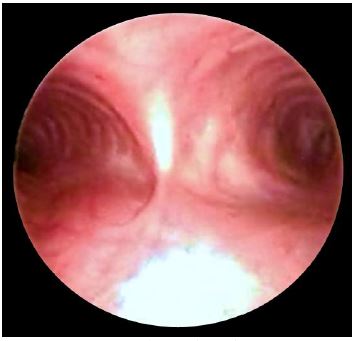

Three points of external compression are visible at oesophagoscopy i.e. aortic arch, left main bronchus and diaphragm (Figure 22). The left main bronchus crosses the oesophagus anteriorly and indents it below the aortic arch (Figure 23).